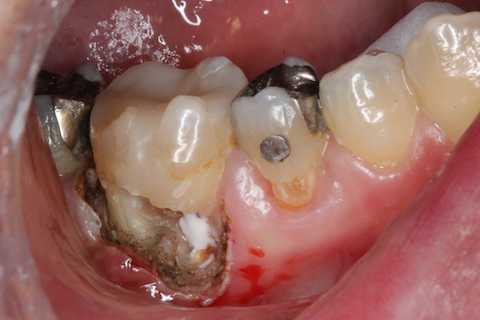

残根上のCR8 2025.10.28